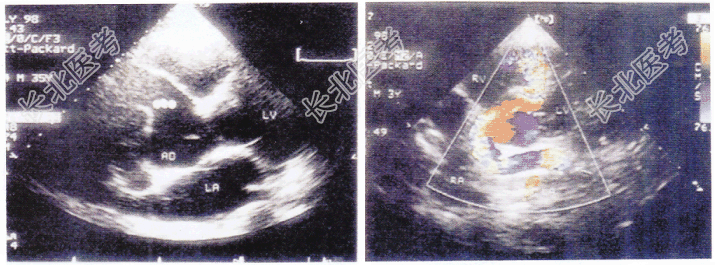

- 单项选择题如图二维和彩色多普勒超声心动图所示,该病例最有可能的诊断是

A、冠状动脉起源异常

B、室间隔缺损

C、川崎病

D、冠状动脉瘤

E、右冠状动脉瘘